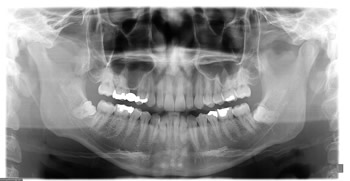

ヨシダ社 パノーラ

常に強力で安定したエネルギーのX線を連続的に照射できる直流方式を採用

デジタルレントゲンの最大のメリットは、少ない被爆線量で鮮明な画像が得られることです。

従来のレントゲン撮影法よりも最大1/10 の線量でクリアな画質なのです。

しかも現像の手間が必要ないので、画像はほぼ瞬時に表示されます。

現像液などの廃液も出ないのもデジタルのいいところ。

環境にもやさしいのです。保険診療の適応なのでご安心ください